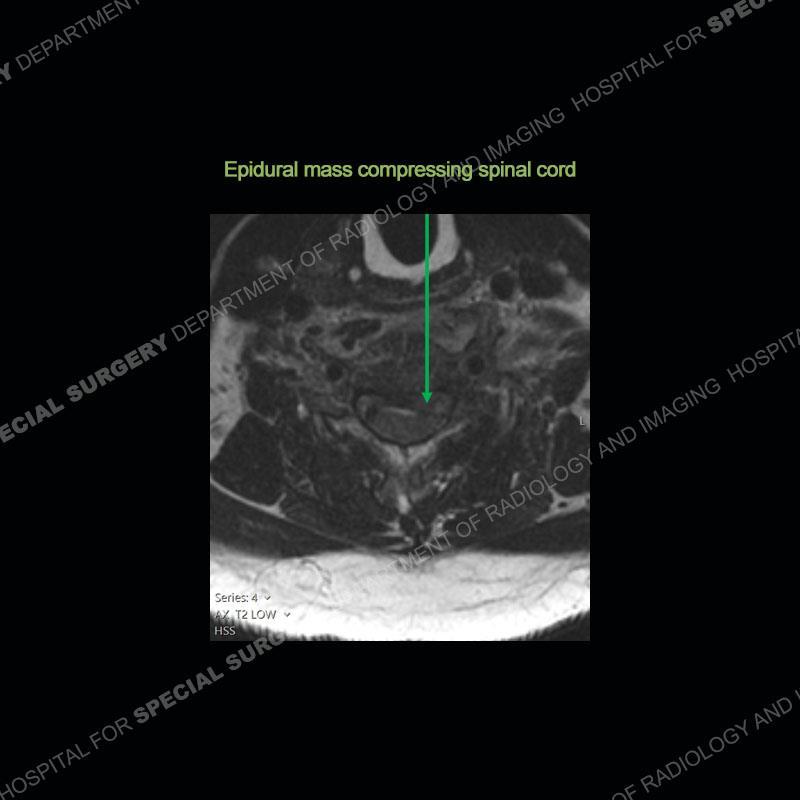

The radiographs demonstrate a prevertebral soft tissue fullness centered at C5-C6 that persists even on extension. There is a slight loss of disc height at C5-C6. The CT more readily shows the prevertebral soft tissue swelling at C5C6 where there is a punctate focus of gas. On the MRI, there is a marked amount of edema and a heterogeneous collection in the prevertebral soft tissue at C5-C6. Edema is present of the C5 and C6 vertebral bodies with a loss of the normal architecture about the disc space. A heterogeneous epidural collection has formed that causes compression of the spinal cord asymmetric to the left side and also precipitates severe left sided neural foraminal stenosis.

Diagnosis: Spontaneous Retropharyngeal Abscess (RPA) with Discitis/Osteomyelitis, Epidural Abscess, and Cord Compression

Spontaneous RPA in the non-immunocompromised, adult population is an extremely rare occurrence. RPA most frequently occurs in young children and most typically after a URI. It may be associated with torticollis in Grisel syndrome. In the adult population, the pathomechanism is not well understood with some suggesting a hematogenous spread or perhaps a seeding from the adjacent aerodigestive tract. The abscess as in this case can extend to involve the vertebral column and then the neural elements. At times, this process can be treated with antibiotic therapy alone but when there are neurologic symptoms and especially progression of neurologic symptoms, surgical intervention is warranted. In this case, given the extent of the process and the patient’s clinical situation, a corpectomy with fusion was performed in addition to antibiotics.